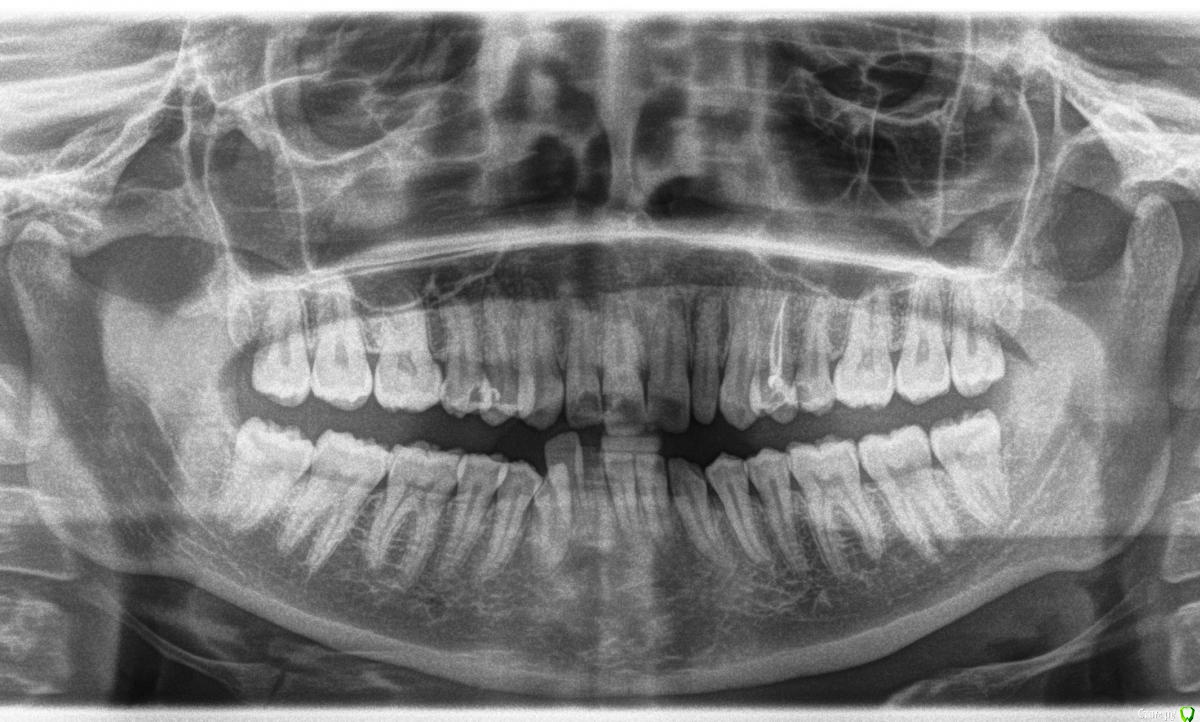

Человек Опубликовано 13 января, 2015 Поделиться Опубликовано 13 января, 2015 Здравствуйте! Требуется удалить боковой нижний резец, зуб 42. 1. Насколько сложная ситуация?2. Насколько велик риск повреждения соседних зубов?3. Можно ли при удалении этого зуба передвинуть на его место соседний клык, так чтобы он встал в зубной ряд? или лучше не рисковать? Спасибо. Ссылка на комментарий